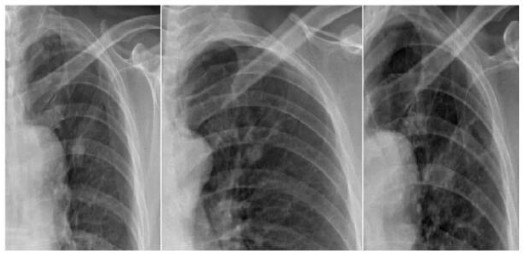

案例一:

第一年 第二年 第三年

案例解析:

在该案例中,病患在单一胸片检查中,诊断出左上肺高密度结节影,前两次在胸片摄影检查得出的诊断结果并无大碍。相隔一年再去复查被误诊为“结核硬结灶”,并针对此而治疗。但是,到了第三年之后,再次诊断发现结节影明显增大,后才被确诊为是肺癌,但为时已晚;如使用具备可视化点片功能的DR设备,胸片与胸透无缝结合,在透视下对“高密度结节影”全方位、多角度的高清点片获取更多的确诊信息,进一步病理分析,第一时间得出确诊结果,做到早发现、早治疗,结果将会截然不同。